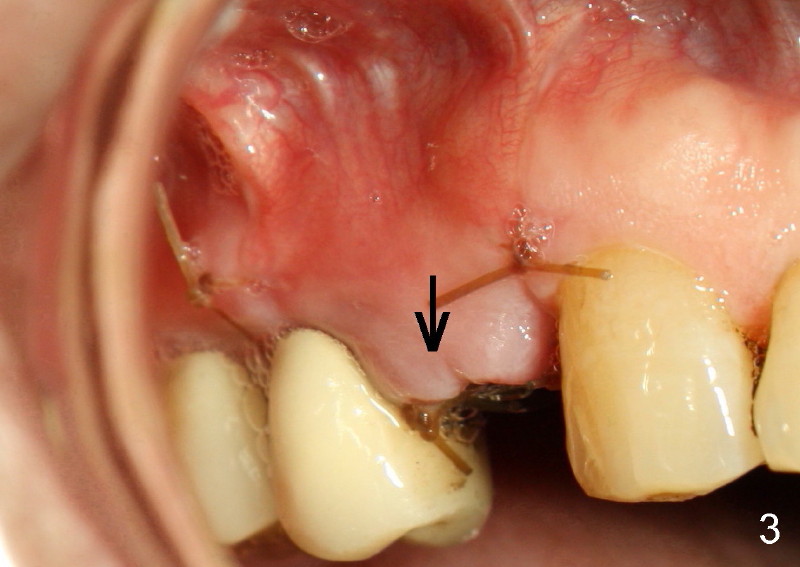

Sixty-eight year old healthy man has had multiple implants.  He readily accepted immediate implant when the tooth #5 had subgingival fracture of the lingual cusp (Fig.1).  A 5x20 mm Tatum screw implant was placed immediately after atraumatic extraction and bone expansion (Fig.2 I).  Implant rough surface was exposed buccally and lingually when the implant was placed equigingivally proximally.  Two buccal accessory incisions were made.  The flap was raised with scoring the periosteum underneath, advanced downward (as shown in Fig.3 arrow) and sutured to the lingual papilla.  The buccal aspect of the implant is covered, whereas the lingual rough surface remains partially exposed (Fig.4 arrow), assuming that the palatal mucoperiosteum is tough to advance even with release incisions.

Fig.3 and 4 are taken 1 week postop, whereas Fig.5 and 6 (mirror view) are taken 2 weeks postop.

Fig.7-9 are taken 3.5 months postop.  Buccal gingiva appears to have elevated (Fig.8 arrow, as compared to Fig.5 B).  The rough surface seems to have been partially covered by lingual gingiva (Fig.9 arrowheads, as compared to Fig.6).